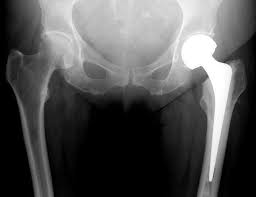

Upload Date: January 23, 2019 Full Size Image Dimensions: 256 × 197 Image Parent Post: Ημιαρθροπλαστική Ισχίου

Ημιαρθροπλαστική Ισχίου-ΑΚΤΙΝΟΓΡ